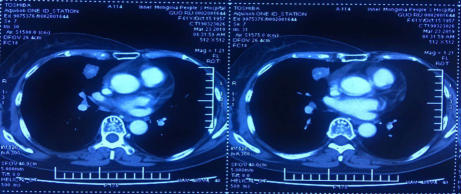

2018年12月,疾病再次进展。转移灶大小:25×27mm。

右肺中叶内侧段结节25×27mm,较前增大纵膈、右肺门多发增大淋巴结